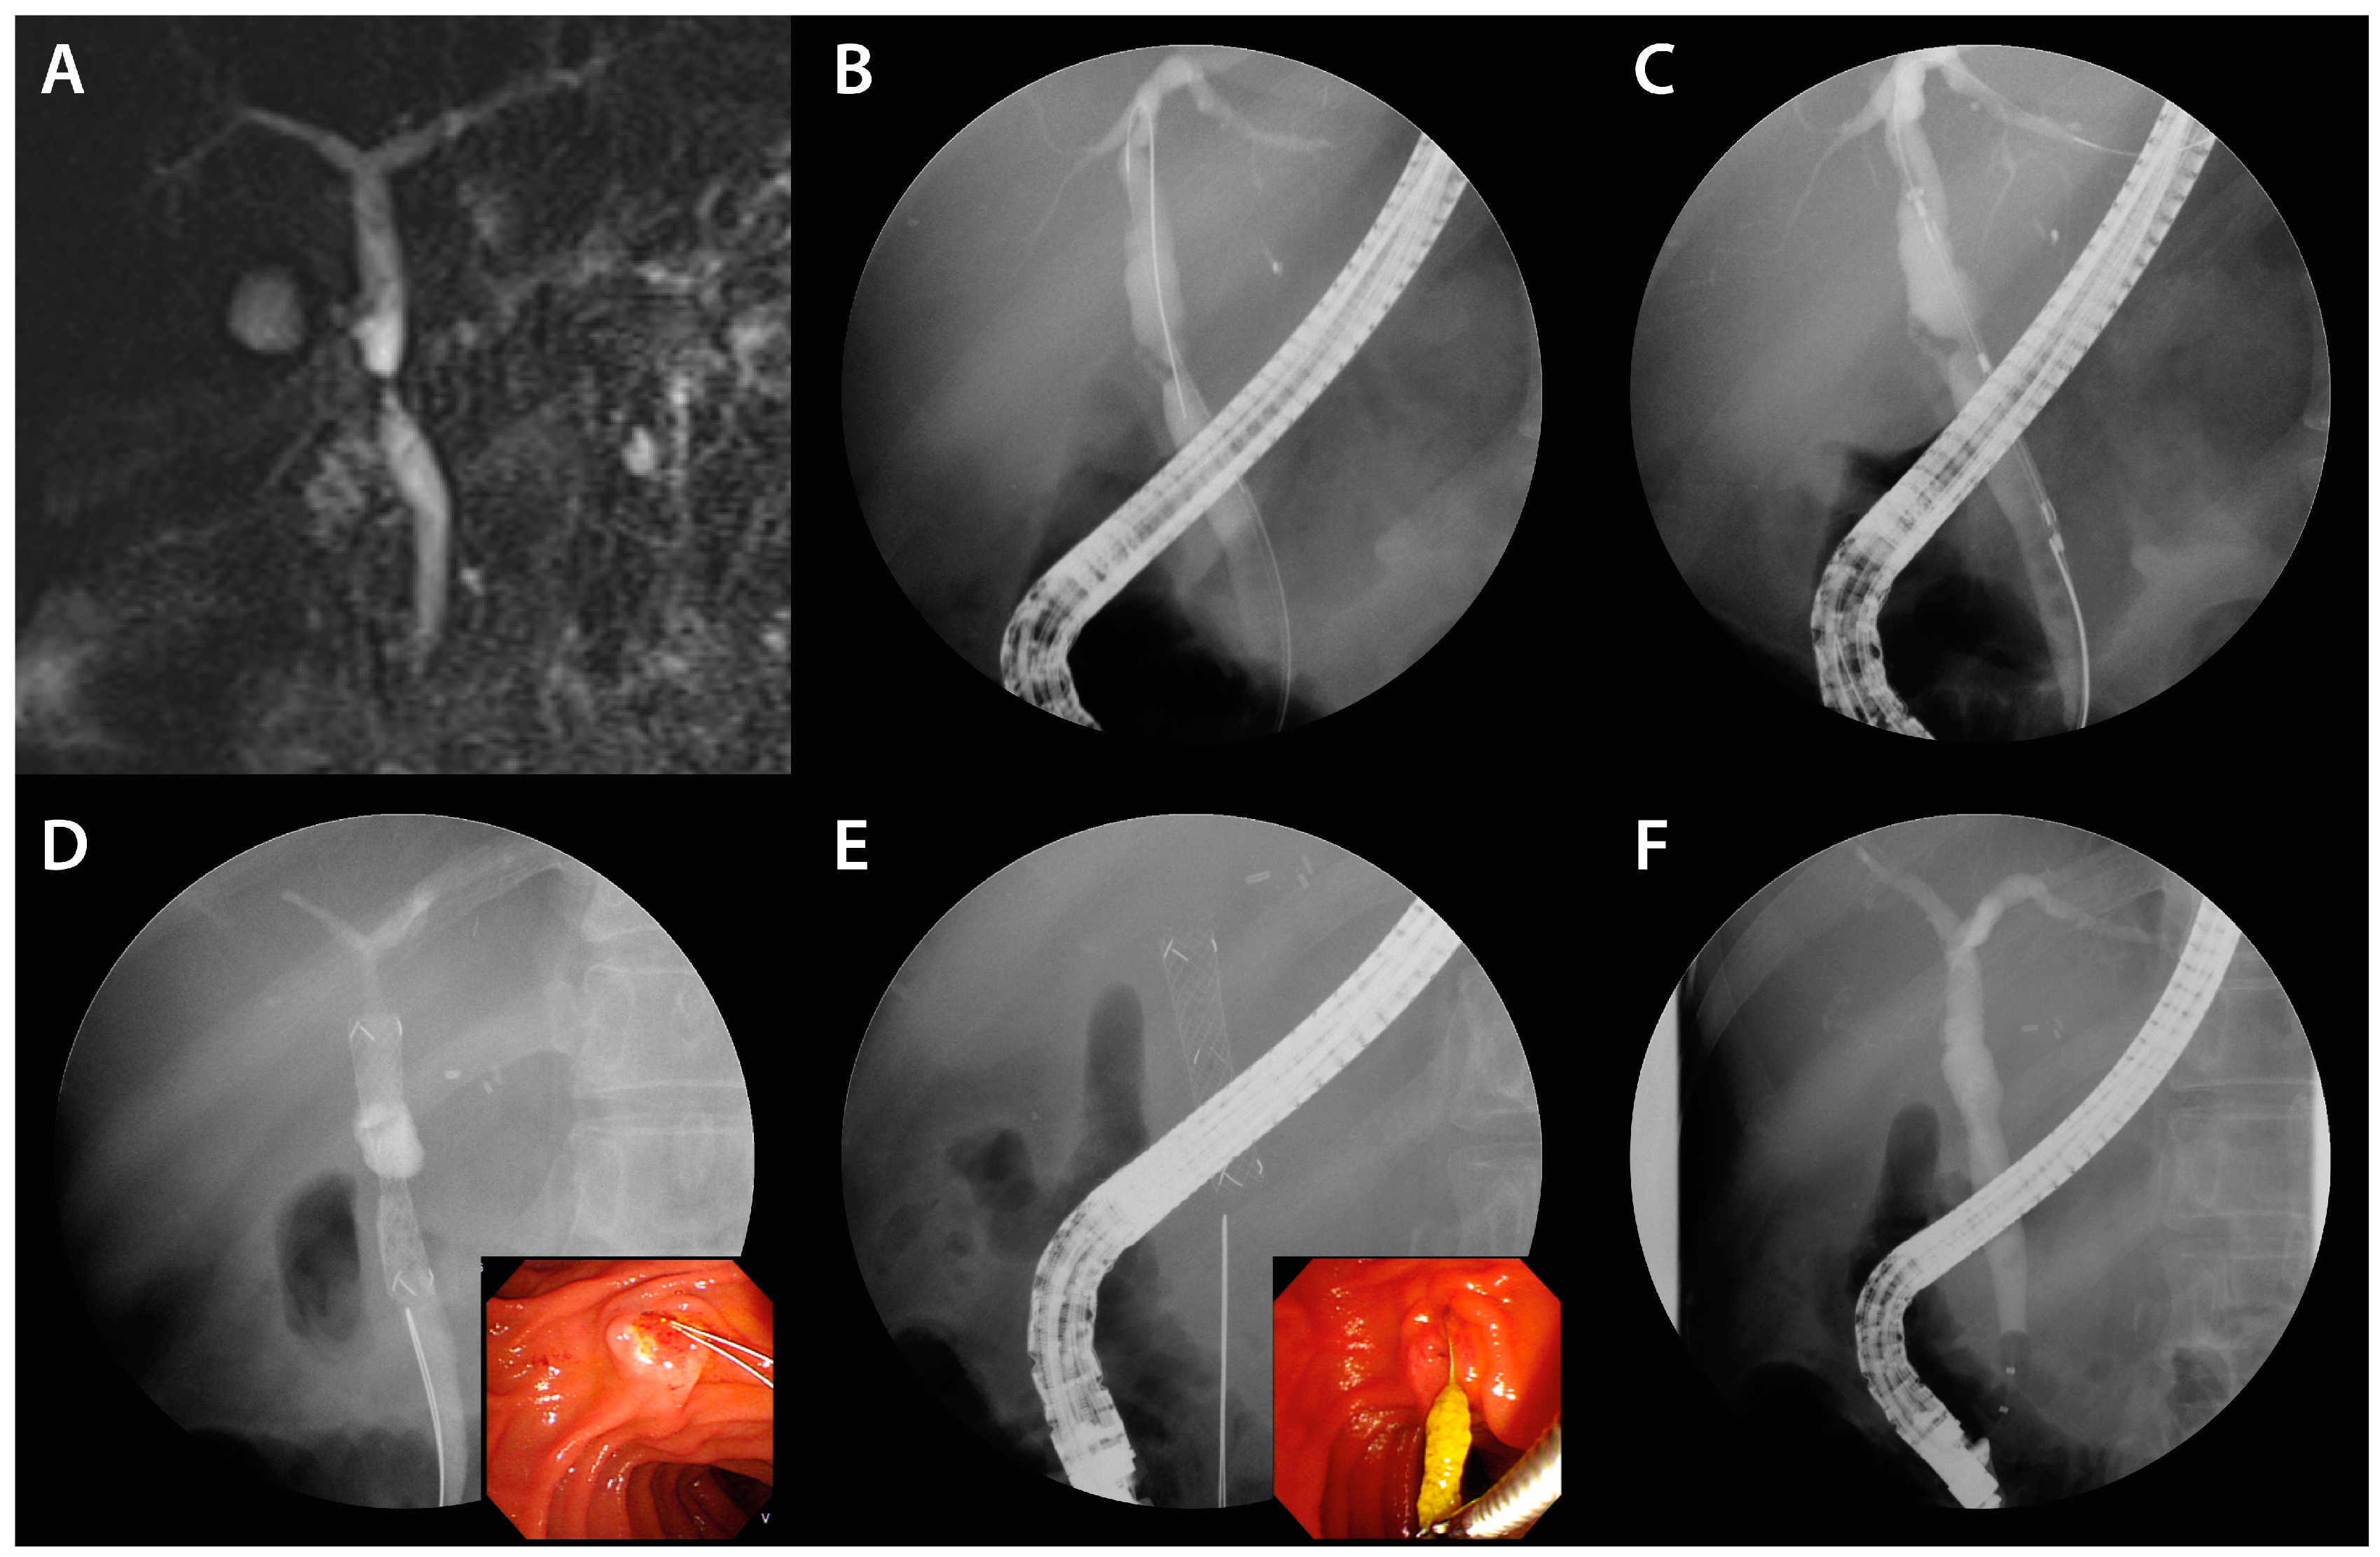

In instances where the stenosis persisted, the FCSEMS was reinserted. The stent was removed by pulling the retrieval string, which was visible in the duodenum, using endoscopic graspers (Figure 3E). After the procedure, patients were scheduled at 3 month intervals based on previous studies and considering the risk of stent occlusion and cholangitis [15], and were followed up every 1 month after stent placement to monitor for signs of stent occlusion. Cycles of FCSEMS deployment via ERCP were performed for up to 12 months or until complete resolution of BBS. The FCSEMS was positioned using the rendezvous technique when biliary cannulation was challenging or when a patient had previously undergone percutaneous transhepatic biliary drainage (PTBD). Moreover, in cases of BBS proximate to the hilar region, a precautionary measure was employed: a 7-Fr plastic stent (Zimmon, double pigtail type; Cook Medical) was pre-emptively placed prior to the FCSEMS insertion, especially in scenarios indicating potential blockage of adjacent biliary branches by the FCSEMS. In the subset of patients exhibiting multiple BBS presentations, as many as two FCSEMS were judiciously deployed to address each stenotic site.

Figure 3.

FCSEMS treatment of biliary anastomotic stricture after DDLT. A case of biliary anastomotic stricture that developed after DDLT for alcoholic cirrhosis and treated with FCSEMSs is presented. (A) A magnetic resonance cholangiopancreatograph was performed to visualize the shape and length of the stricture. A common bile duct stricture is shown. (B) A common bile duct stricture was observed on cholangiogram. (C) An FCSEMS (8 mm in diameter, 4 cm in length; KAFFES) stent was deployed so that the central radiopaque marker was centered in the stenosis. (D) The FCSEMS is shown at the stricture site, and the retrieval string is located at the duodenum (color figure). (E) After stent indwelling for 3 months, the FCSEMS was found to be completely self-inflating, and the FCSEMS is removed by grasping the retrieval string using grasping forceps (color panel). (F) After three months of FCSEMS, including one replacement, the stent was removed and the biliary anastomotic stricture resolved.

A case manifesting common bile duct (CBD) stricture subsequent to DDLT found resolution after a three-month FCSEMS application (Figure 3).